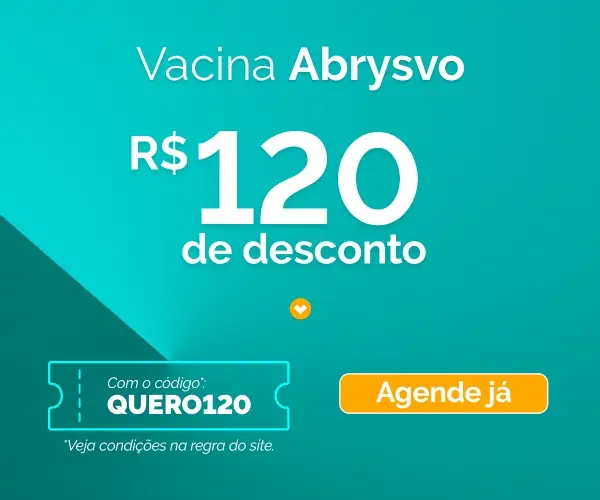

Uma gestação é separada em 3 trimestres e cada um deles corresponde a um intervalo de semanas.

Quer saber em detalhes quais são? Confira o calendário de gestação abaixo. Ele funciona como uma tabela de gravidez e vai te ajudar a entender melhor: